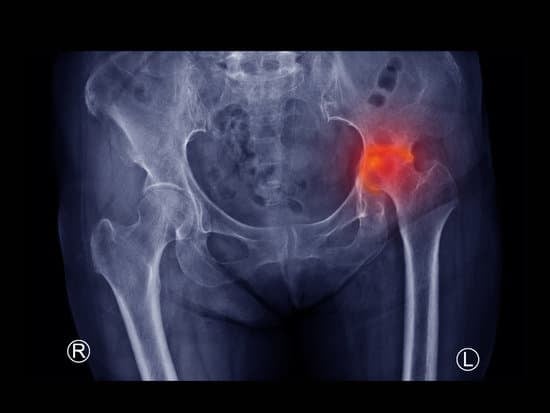

X-ray 검사

대퇴골두의 뼈 상태를 확인하는 데 X-ray 검사가 가장 많이 사용됩니다. 초기에는 뼈의 변형이 명확하지 않을 수 있으나, 진행됨에 따라 뼈의 괴사와 변형을 확인할 수 있습니다.